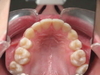

Sur une radio panoramique on la localise : couchée, plus ou moins haute, au palais ou côté joue … tout est possible ! Ce que nous pouvons remarquer sur les radios de notre patient.

1e Radio : Position de la canine incluse